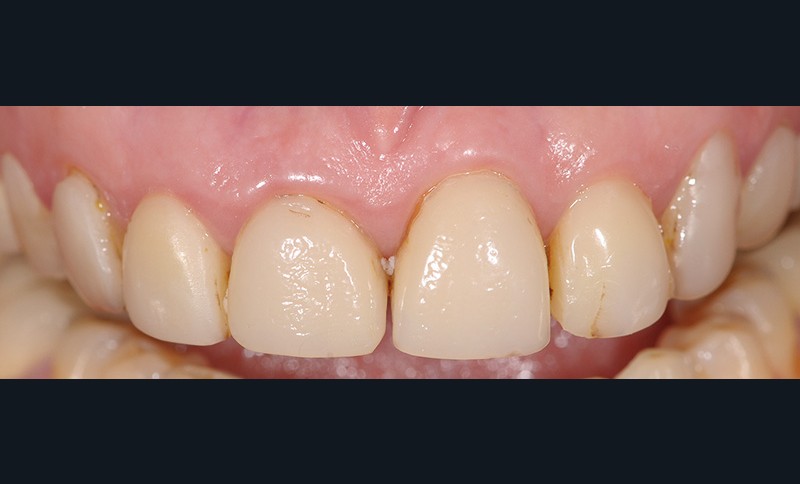

Avant de répondre aux différentes interrogations cliniques, il faut analyser la situation par des évaluations cliniques (état coronaire, situation endodontique, environnement parodontal) (fig. 1) puis, parfois, il est nécessaire de poursuivre cette étude préthérapeutique à l’aide d’outil de simulation comme l’articulateur (fig. 2), de techniques radiologiques en 3D. La conjugaison du recueil des informations et de l’analyse de la situation va nous permettre de proposer une solution en rapport avec la problématique médicale globale.

Ainsi, chez ce patient (fig. 3) quelle(s) solution(s) thérapeutique(s) peut-on envisager pour répondre au problème de mobilité dentaire en respectant son souhait de conservation ? Doit-on envisager d’extraire toutes les dents et d’avoir recours à une solution implantaire ou existe-t-il une solution fiable de conserver ses dents ?